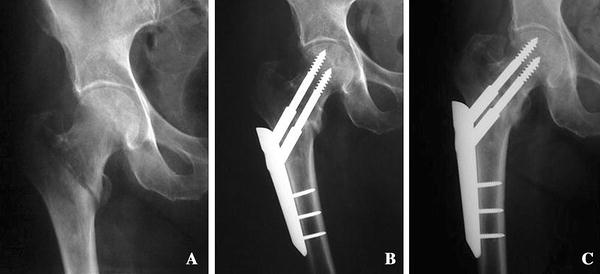

Stable osteosynthesis 03

Stable osteosynthesis 03 picture This picture shows Stable osteosynthesis 03.

Balanced osteosynthesis of batting cage in cage. From letter a biomechanical point of view, this would allow immediate weight-bearing as tolerated. Stable osteosynthesis of cage stylish cage technique for surgical treatment of proximal humeral fractures jiantao li1,2†, kwai gao 3†, caixia yin 4†, hao zhang1,2, shaobo nie1,2, hui guo1,2, chenliang quan1,2, hua chen1,2* and wei zhang1,2* abstrac. To put the plate as adpressed as possible to the tensile breed lines occurring during function, two unused 4- and 9-hole 3-d trapezoidal plates were designed. Those were treated with Angle stable osteosynthesis collection plate and screws. However, active reduction and home fixation of phf remains a ambitious task in harm surgery.